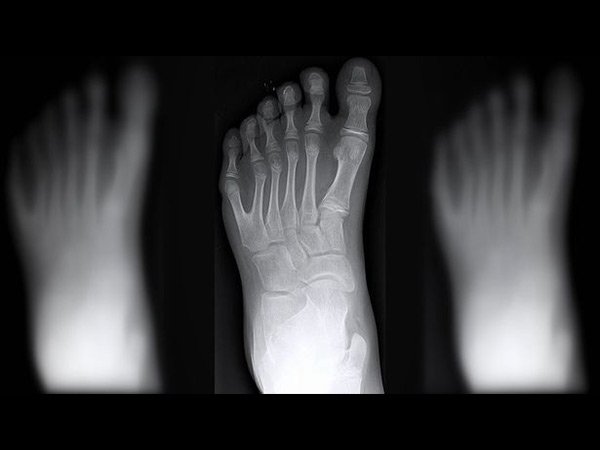

ఆశ్చర్యం కాదు, ఇది నిజం! ఆ కుటుంబంలో ప్రతి ఒక్కరికి 12 వేళ్లు !

వారు కాస్త భిన్నంగా ఉంటారు. అందరికీ చేతికి పది వేళ్లు ఉంటాయి. కాలికి పది వేళ్లు ఉంటాయి. కానీ వారికి మాత్రం పన్నెండేసి చొప్పున ఉంటాయి.

అయితే ఒక కుటుంబానికి చెందిన సుమారు 14 మందికి ఇలా చేతికి పన్నెండు వేళ్లు ఉండడం, కాలికి 12 వేళ్లు ఉండడం కాస్త ఆసక్తికరమైన విషయం.

ఈ ప్రత్యేక కుటుంబం డి సిల్వా అనే పేరుతో పిలవబడుతుంది. ఈ కుటుంబంలోని 14 మంది సభ్యులు ఈ విలక్షణమైన లక్షణాలు కలిగి ఉన్నారు. వీరంతా కూడా 12 చేతి వేళ్లు, అలాగే కాళ్ల వేళ్లతో జన్మించారు.

సాధారణంగా ఇలాంటి పరిస్థితి చాలా అరుదుగా ఉంటుంది. ఈ పరిస్థితికి 'పాలిడాక్టిలీ' అనే జన్యు సిండ్రోమ్ కారణం అవుతుంది. ప్రతి 1000 మందిలో ఒకరు మాత్రమే ఇలా పుడుతుంటారని ఒక పరిశోధనలో తేలింది.